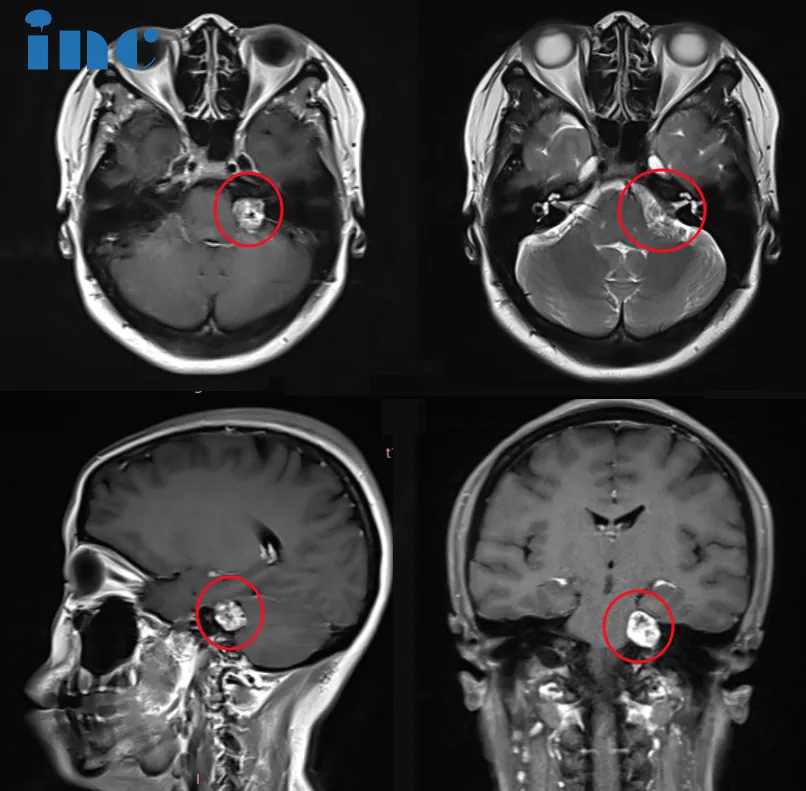

影像

直到2023年7月,吳女士的癥狀全面加劇——左側(cè)頭皮、臉頰、太陽穴、舌頭、嘴角紛紛發(fā)麻,左側(cè)頸部有沉重感,耳朵疼痛難忍。這一次,她終于前往醫(yī)院進(jìn)行了全面檢查。

檢查結(jié)果讓所有人震驚:左側(cè)聽神經(jīng)瘤。

更令人擔(dān)憂的是,術(shù)前檢查顯示吳女士已經(jīng)出現(xiàn)輕微的腦干受壓,面部和三叉神經(jīng)受累的跡象(左嘴角刺痛等)以及聽力障礙。這個(gè)診斷解釋了她多年來所有的癥狀,也讓她面臨一個(gè)艱難的抉擇。

診斷